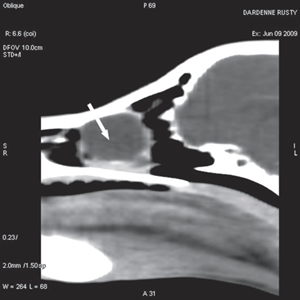

For further assessment, the dog underwent computerized tomography (CT) that extended from the lower aspect of the orbits through the nasal cavity. The computerized tomography studies were carried out using a 16-row multislice CT scanner (Philips Brilliance Mx 8000 IDT 16 CT Scanner, Philips Medical Systems, Hamburg, Germany). Two-millimeter computerized tomographic images (100 mA, 120 kV) were acquired, with both bone and soft tissue algorithms, from the orbital region to the rostral part of the nasal cavity to cover the length of the lacrimal duct. A 10-mm-wide bone defect was observed in the dorsolateral part of the right maxillary bone, rostral to the orbital cavity, at the level of the P3 to M1 tooth roots (see image). Its borders were smooth, and no proliferation could be seen. A soft tissue density, 17 mm wide and 20 mm long, occupied the ventrolateral part of the nasal cavity at that level, slightly protruding through the bone defect and severely reducing the nasal cavity diameter. After IV iodinated contrast injection (ioxitalamate 700 mg/kg IV, Omnipaque 350®, Guerbet, Roissy CDG, France), a thin rim enhancement was observed around this mass, suggesting the presence of a thin wall (Fig. 3).

Figure 3a Transverse view Figure 3b Sagittal view Figure 3c Coronal view

Fig. 3 a,b,c : computerized tomography (CT) imaging at the orbit and pterygopalatine fossa level. A well-circumscribed cystic structure (arrows) can be identified extending into the orbit and nasal cavity.